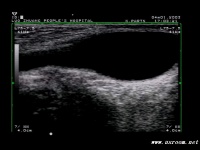

B超检查可进一步明确诊断,对疑为睾丸肿瘤引起的继发性睾丸鞘膜积液有重要意义、

4.B 超检查可明确诊断。